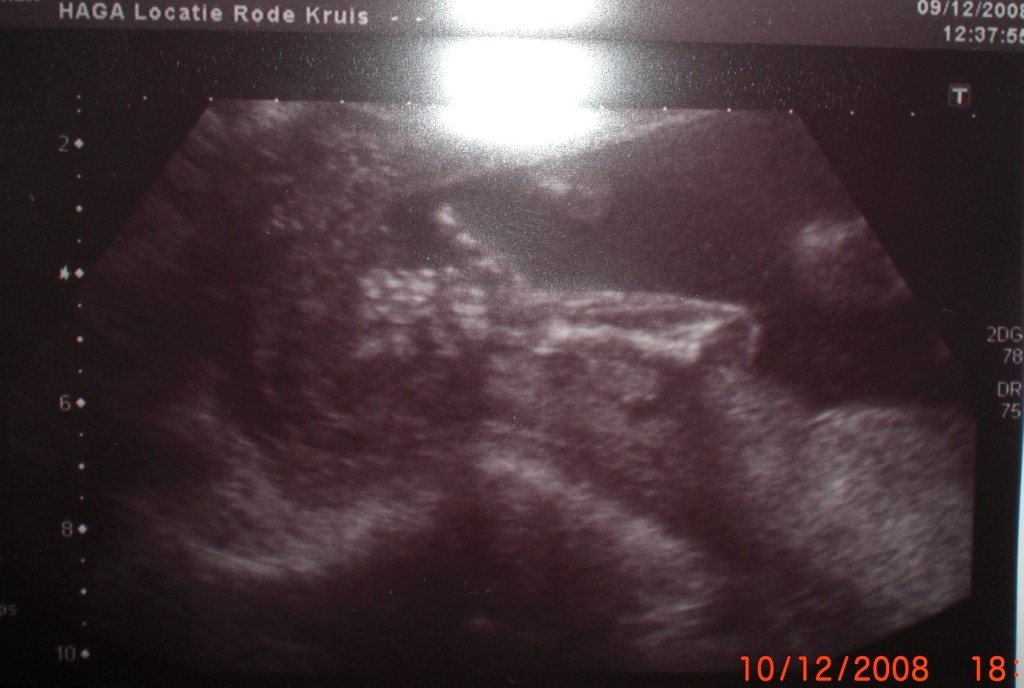

Ja powinnam mieć doła, bo po wczorajszych badaniach w szpitalu i godzinnym USG nadal nie wiem co z moim synkiem.

Jutro kolejna wizyta w szpitalu, tym razem ze specjalistą od wad genetycznych. Ponieważ mój synek ma jeden z tak zwanych "soft markerów" wskazujących może na jakąś wadę, to musieli go dokładnie obejrzeć i poszukać innych jeszcze oznak, że coś jest nie tak albo wukluczyć całkowicie jakąkolwiek chorobę. Jutro dostanę raport z USG i do jutra mam się zastanowić, czy jak coś chcę amniopunkcję.

Powiem Wam, że jakaś silna się czuję psychicznie,jak o tym myśle i aż sama się dziwię....ale to może dlatego że synuś pokazał mi wczoraj, że wszystko jest OK.

( na załączonym obrazku...jak się wklei)